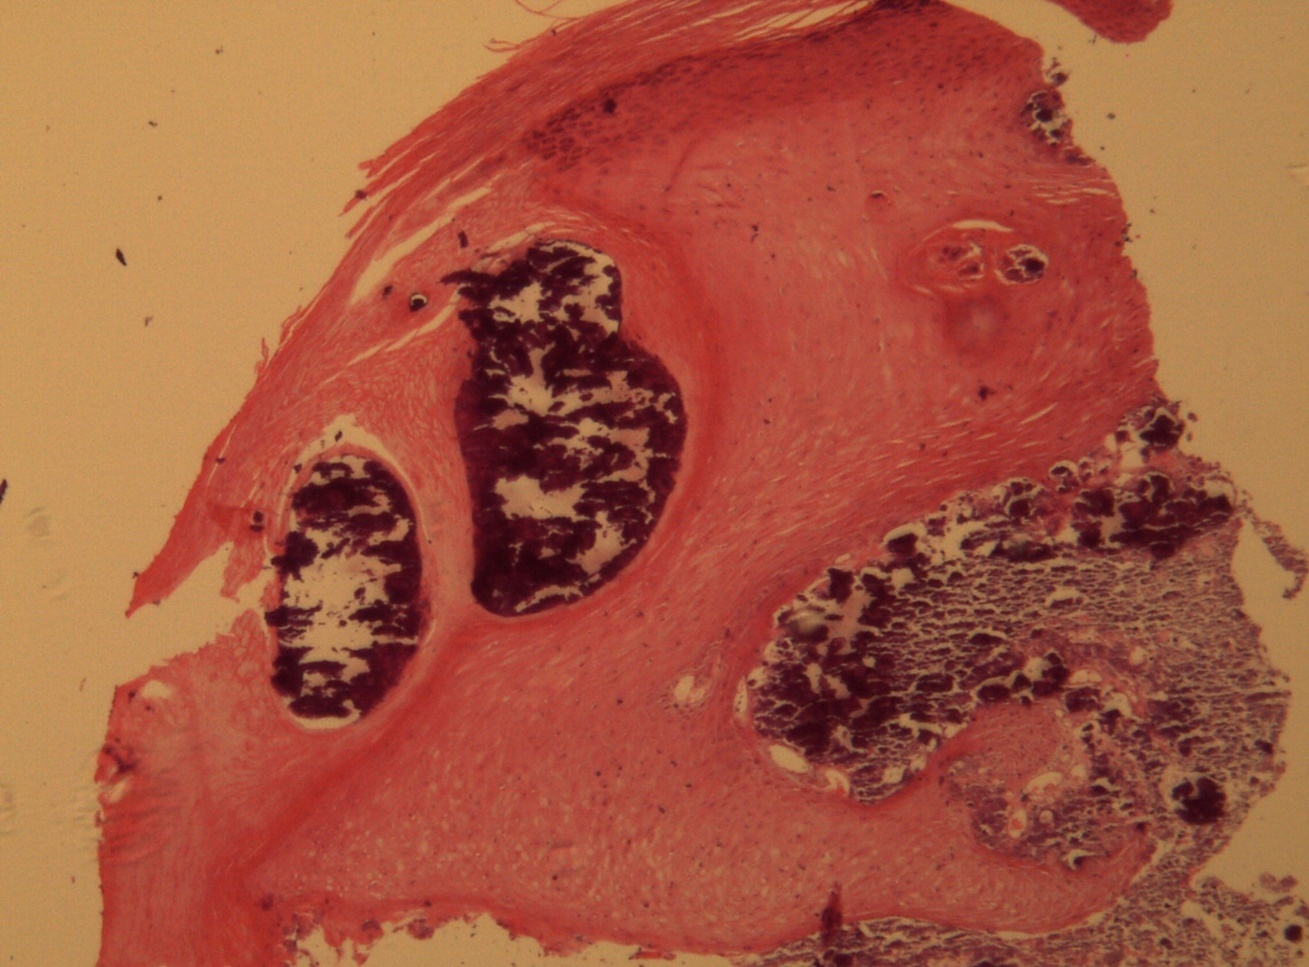

A 9-year-old male patient who was treated in the dermatology service for a progressively growing keratotic nummular dermal lesion on the right knee. With the clinical judgment of viral wart, the lesion was removed. In the Pathology Service, a nummular keratotic lesion of 0.5 cm in maximum dimensions was received, which crackled when cut. Figure 1, Figure 2, Figure 3, Figure 4, Figure 5

Figure 1.Hyperkeratosis, hypergranulosis, proliferation of dermal vessels, and surface and deep calcium deposits. HE. 100x.